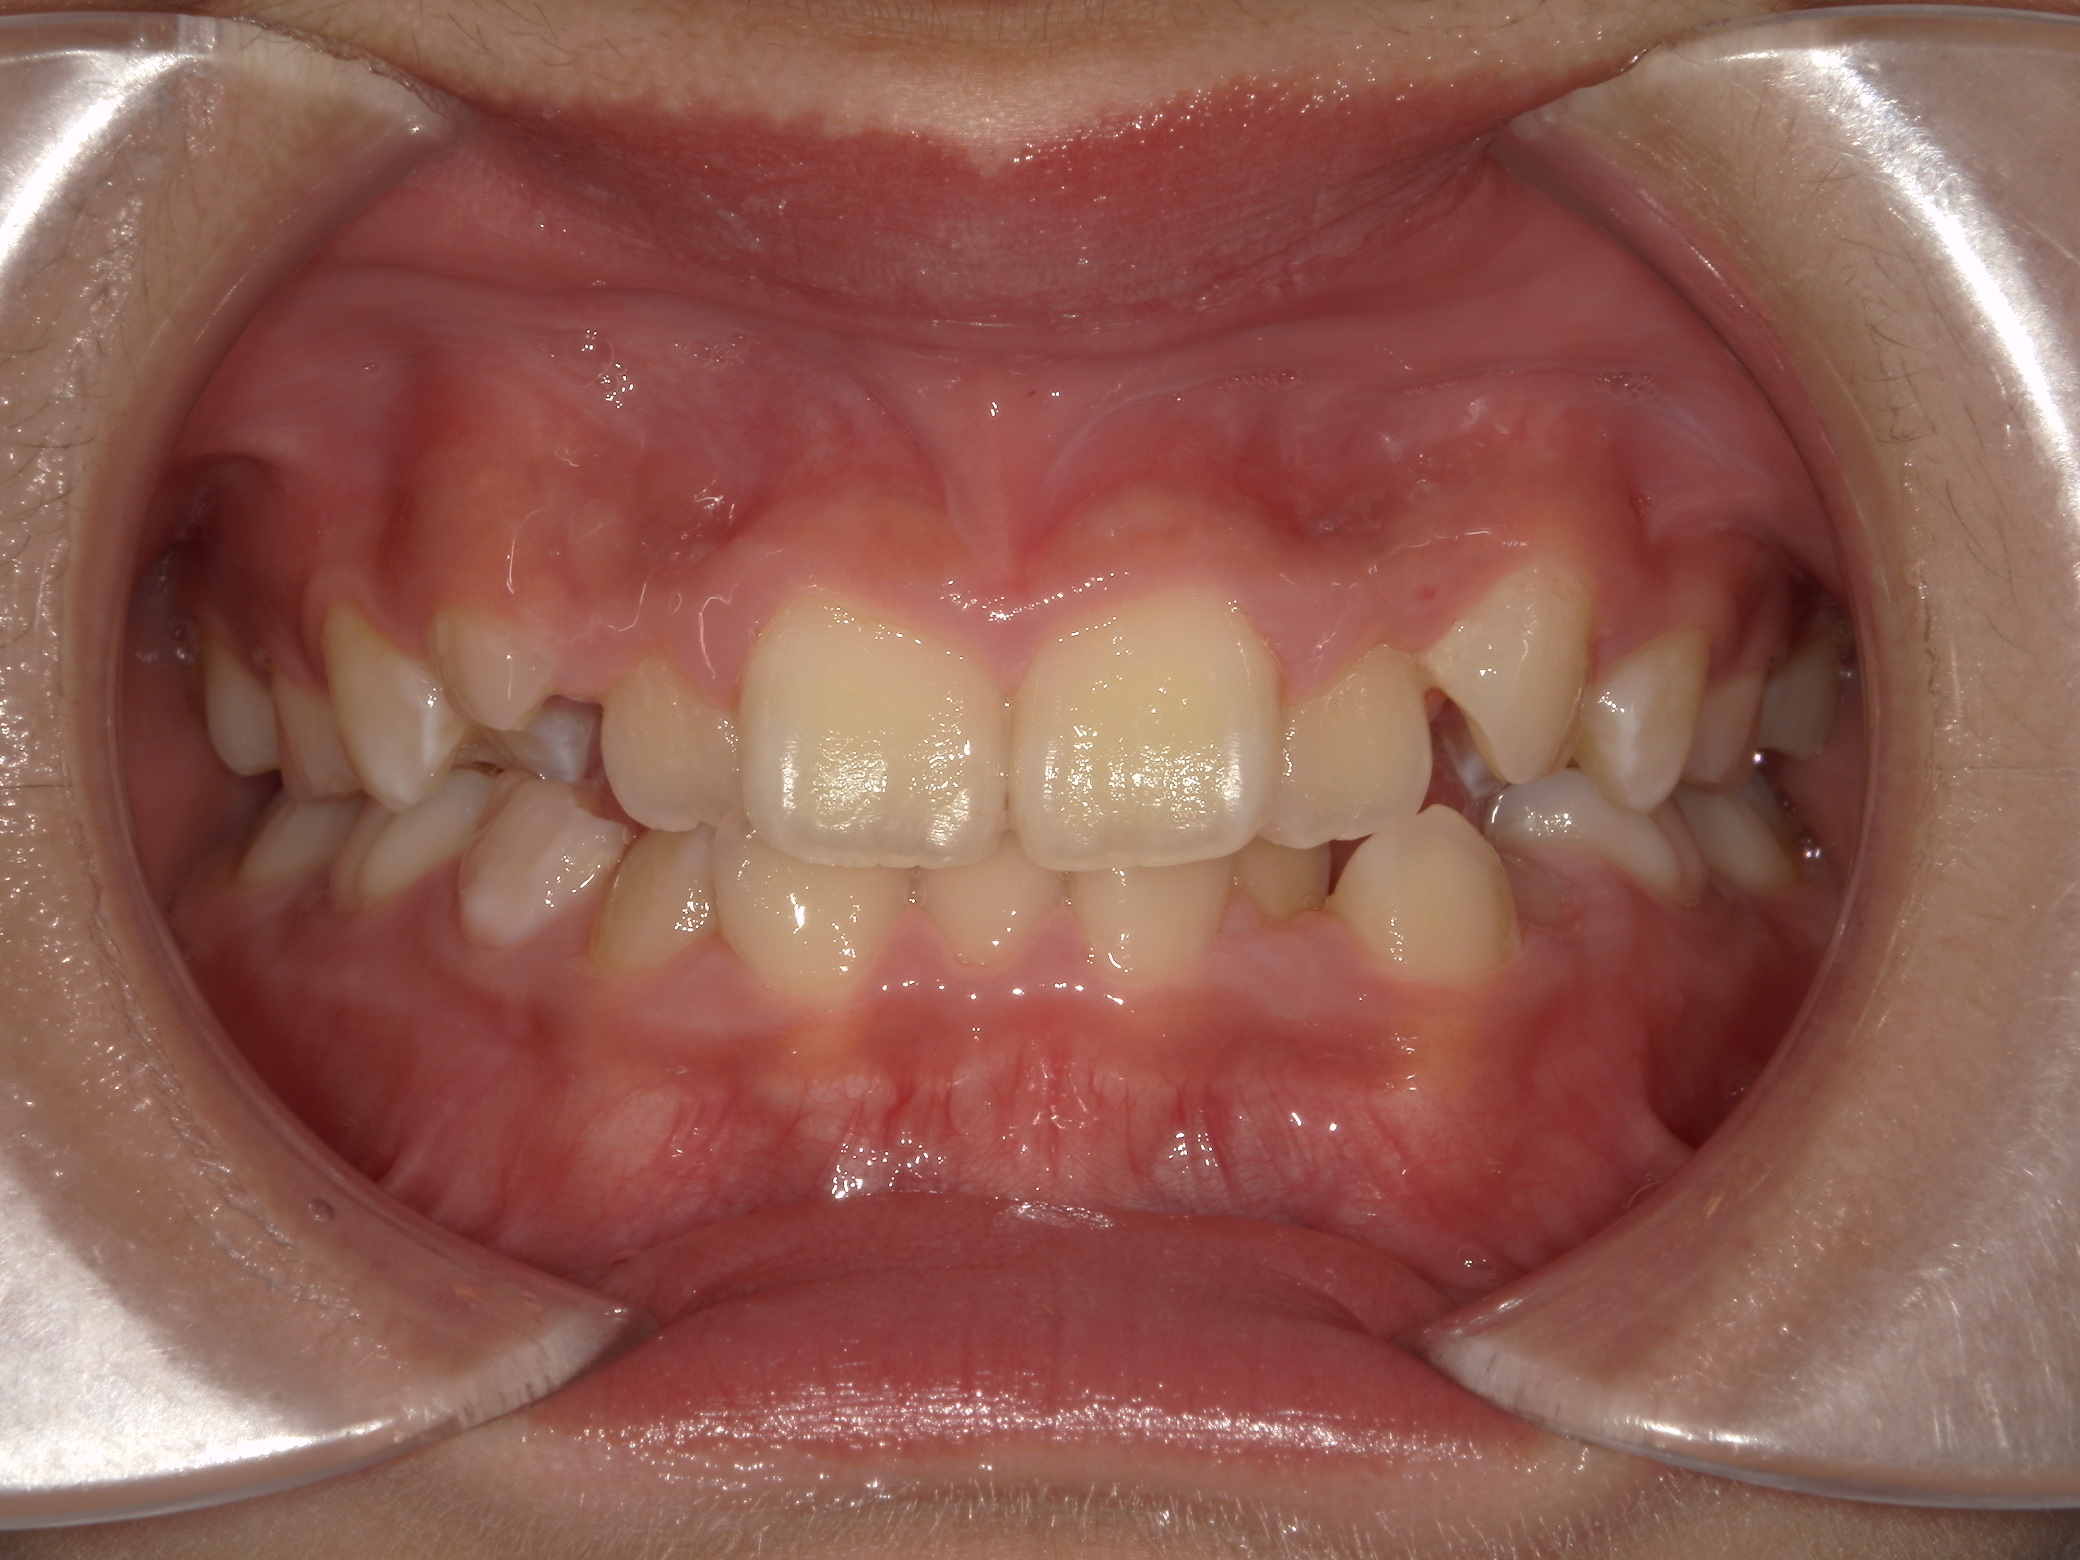

すきっ歯(11歳空隙歯列)

11歳 男性

非抜歯矯正治療

表側ワイヤー矯正

935,000円(税込)

1年2か月

隙間が歯列全体にあり、かみ合わせも深い状態でした。

上下にワイヤーを装着し、かみ合わせをあげながら隙間を閉じています。

副作用:歯根吸収・歯髄壊死・歯肉退縮・隙間の再発